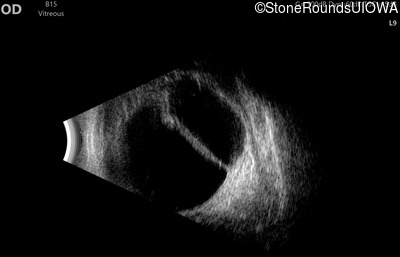

AD Familial Exudative Vitreoretinopathy (IIIE2b)

Age at visit: 23 months

OD OS

This 23 month old male has had nystagmus since shortly after birth. He was born at term (7lbs 12oz).